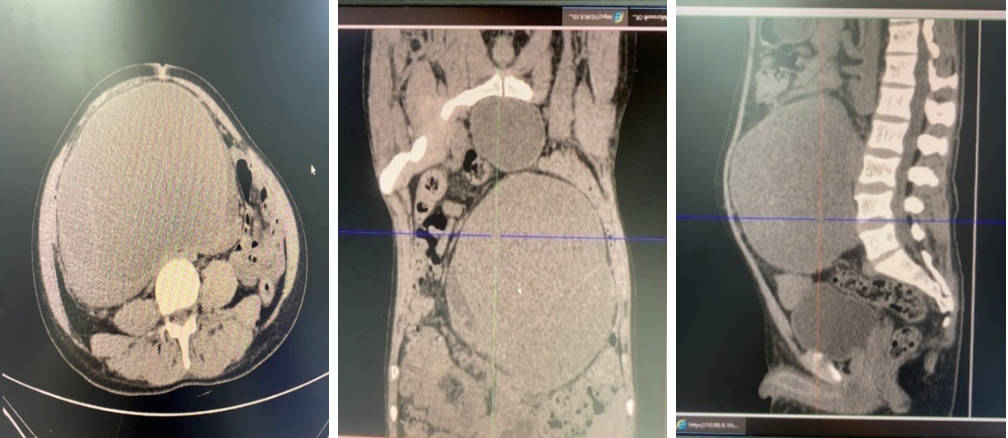

收住入院后,王某表现的时而躁狂、时而冷漠,家属一筹莫展,泌尿外科一病区医护人员一边安抚患者家属、一边疏导患者情绪。在初步查体并进行检查后,明确王某为:马蹄肾,伴双肾实质间巨大囊性占位(大小约 17.4×12.2×21 cm);右侧肾盂增宽积液、输尿管上段部分重复畸形;左侧肾盂增宽,左侧输尿管未见确切显示。

随着检查报告的进一步清晰指示,泌尿外科一病区张刘勇主任团队反复研究、分析后,认为患者马蹄肾、肾囊肿,短时间内显著增大并伴有发热等全身症状,考虑合并囊内感染积脓,腔镜及开放手术治疗风险极大。同时,结合腹部 CT,考虑肠系膜及肠管包裹囊肿,穿刺损伤血管致出血风险极大。